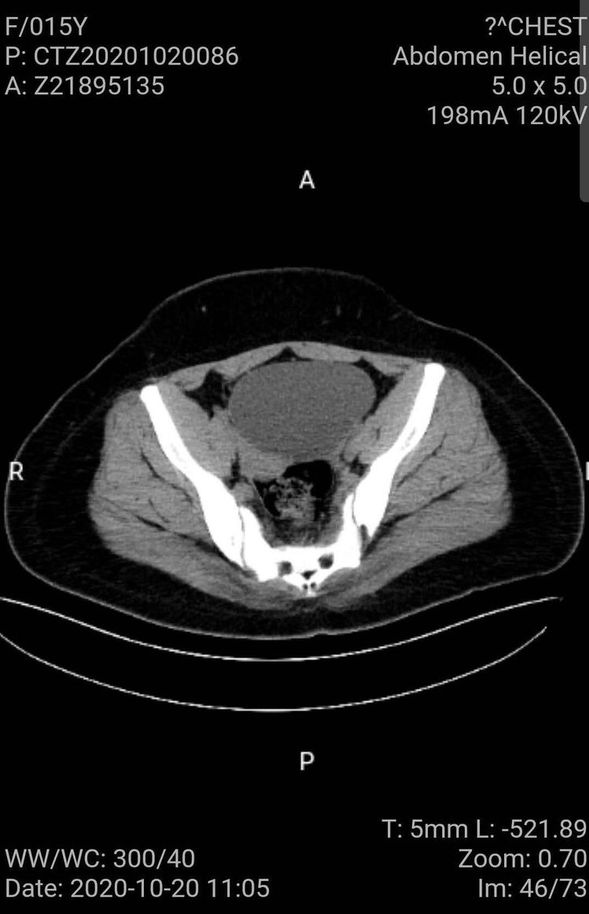

入院后复查的盆腔CT

就在四天前小雨的腹痛加重,消炎药已无法缓解症状,于是家人带小雨到当地医院行彩超检查,彩超显示盆腔囊性包块,大小约10cm,当地医生查看此报告单后告诉小雨的父母立即前往上级医院进行治疗。经多方了解,慕名来到我院妇一科,门诊医生经过仔细询问病史及查体,立即将其收治住院。